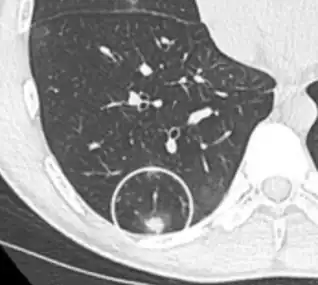

subpleural nodule.[9]

Round well-delineated solid lung nodule with smooth border.[9]

Lobulated nodule.[9]

Spiculated lung nodule.[9]

A "notch sign".[9]

A triangular perifissural node can be diagnosed as a benign lymph node.[9]